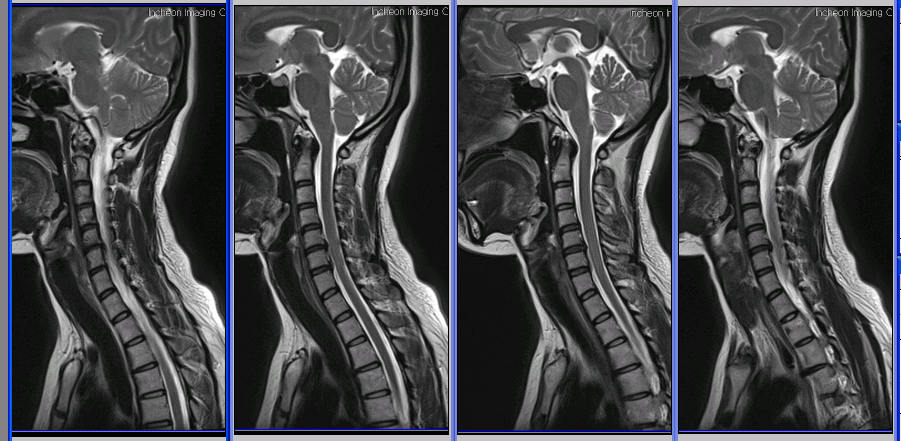

I D : coggili*** (rlagPdu**) ũ mri Դϴ. ȸ ϼ. ȸ Դϴ. , ü Ư Ű 150 Cm ü 47 Kg 39 ȯ 1C.Ż, 1C.ٵǽŰ̻, 1C., 1C., 1C.ڵӸ , 1C.ٽŰ, 1C.ٿ, 1C.ٽŰ, 1C.ٸǷ, 1C.ھ, 1C.ٱ (), 1C.߷ (), 1C.Ƿ (), 1C.ڱӼ , 1C.ڱ ֺ ̻, 1C.ڱ ֺ , 2C.ھȱ , 2C.ھ˷⼺(˷) ḷ, 2C. , 3C.ڱ(), 4C.5C.ھ, հ ̳ , 5C.6C.ڰ հ ̳ 6C.ڸ , 6C. κ Ḳ , 6C.ھ Ḳ , 6C.ڻ , 6C.7C.ھ հ ̳ 7C.Ȳġ, 7C. , 1T.ڼհ ü ̳ , 1T. κ , 4T. , 2T. Ʒκ 3T.ٺ, 4T. ༺ , 5T.ȯ ҷ, 6T., 6T. Ű , 6T.ټ , 7T.˾, 8T. , 10T.ٸǷ, 11T.ȯ 12T.ٰ (), 1L., 2L.Ϻ , 2L.ڴٸ κ 2L. 㰡 , 3L.汤 ̻, 3L.汤, 3L.ٹ̻, 3L.ڹ 3L. 4L Һ Һ, 4L.ڿ, 5L.ڴٸ Ʒκ̳ , 5L.ڹ ٸ ȯ, 5L. , 5L.ڴٸ 5L.ڹ߰ ̳ ȭŸ̳ 5L.Ƹ 㰡 õ().° ̳ , õ().شٸ, ()κп ̻ ܵ. ()ũ( ߰Ż), ũ(߰Ż)ġ, հ , ġ, , Ḳ ġ Ǵ , , ȱ ǰϰų ڸ, , ڰ , , Ǵ ġ , 㸮 ̳ ġ ٸ ġ Ƹ ġ ġ ġ ߰ ġ ħ , ġ ħ Ʈ 氨 , dz, , Ǵ ġ 帶, ɱٰ, ɺ Ƿ ġ ȭҷ ġ ͳ ˻ڷ õ 1. 2009 2 7 ũ(5,6,7 ߶ ) . ġ ̸ 6 ġ . 6 CTԿô ڸ ⵿ ġḸ . 2. Ӹ ߰ ø. (㸮 ʾ ӽ(9) ݺ ٸ ִٰ 3-4 ) ε 3. ϴ ¸ ̶ Ʈ Ǵ |